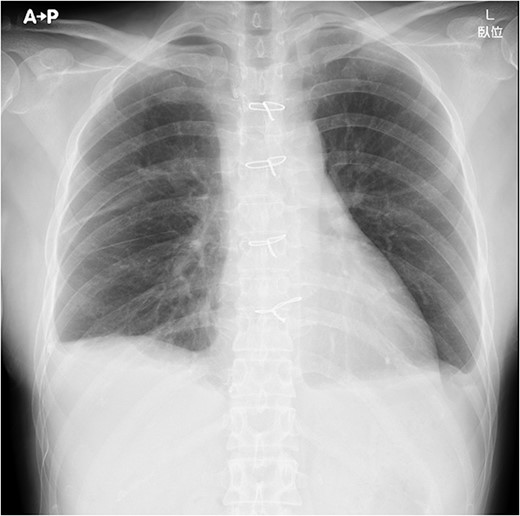

On post-operative day 17, she visited our hospital for a routine follow-up, and her chest X-ray revealed a massive right pleural effusion (Fig. 3). Therefore, she was re-admitted to our hospital and right chest drainage was performed. Milky and turbid fluid was drained with an amount of ~3100 ml. The biochemical analysis of pleural fluid revealed a triglyceride level of 1420 mg/dl, and we confirmed a diagnosis of chylothorax. She received fasting and total parenteral nutrition. The fluid via chest tubes returned to be clear with its amount of <200 ml for a day.

Chest X-ray on post-operative day 17 revealing massive pleural effusion.